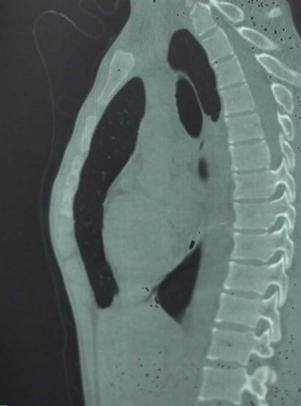

漏斗胸圖片

漏斗胸的